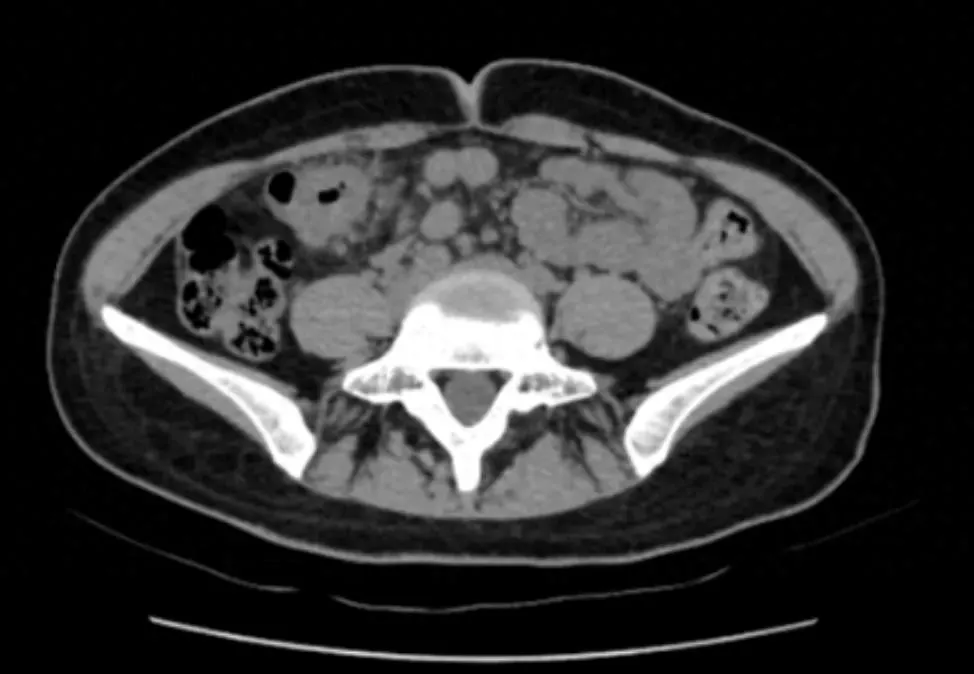

“脐周疼痛对应的多是小肠问题,右上腹的包块却指向肝胆、结肠等器官,这两者对不上。”医生立刻警觉起来,当即安排王女士做腹部 CT 检查。影像结果很快出来: 结肠近肝曲处肠壁可疑增厚,肠腔狭窄 ——这个信号让诊疗团队的神经瞬间紧绷。